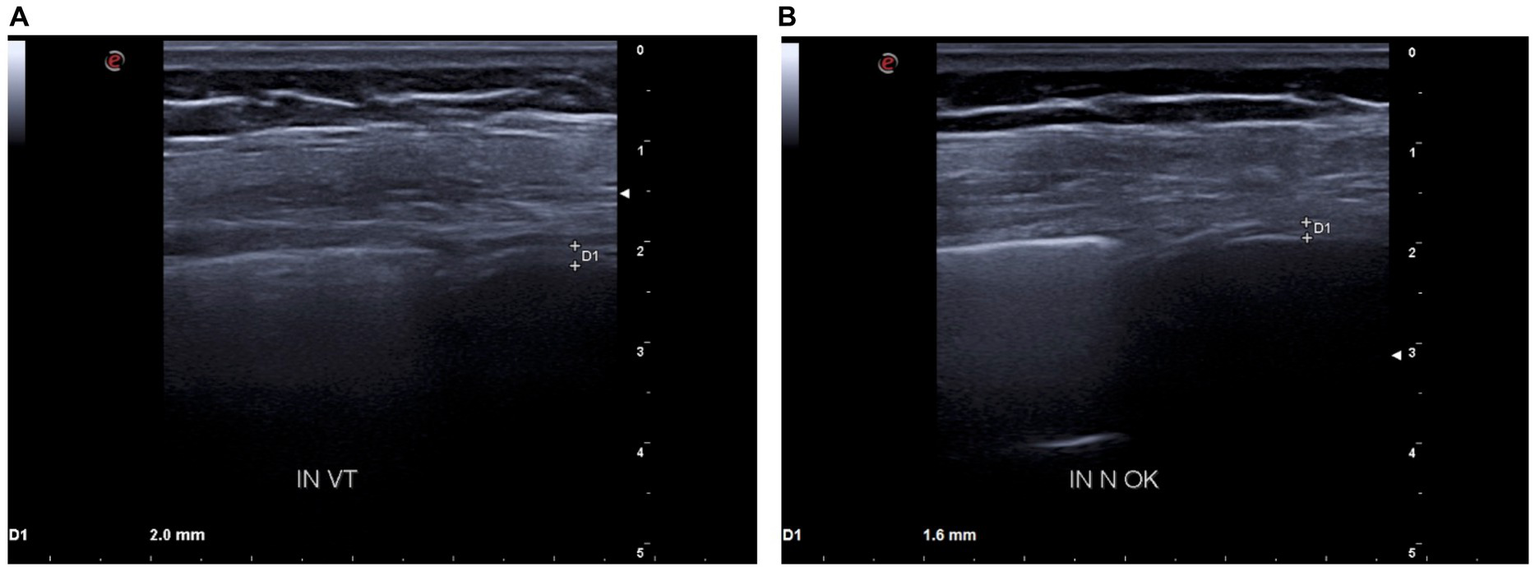

Figure 3

(A) D1: tidal volume inspiratory thickness before BDP/FF/G. (B) D1: tidal volume inspiratory thickness after BDP/FF/G.

Because of these findings and clinical worsening, inhaled therapy was changed from BDP/FF to triple fixed-combination BDP/FF/G. After a week of therapy, the ACQ-5 score decreased to 1.2, and follow-up functional lung tests yielded the following results (Figure 1B): FEV1, 1.20 L (56% of predicted; +0.32 L/+36.4%); FVC, 1.78 L (63% of predicted; +0.44 L/+32.8%); FEV1/FVC ratio, 67.43% (+2.7%); PEF, 3.77 L/s (65% of predicted; +48.4%); RV, 1.48 L (65% of predicted; −1.11 L/−42.9%); TLC, 3.26 L (61% of predicted; −0.67 L/−17.0%); RV/TLC ratio, 45.49 (−30.9%); FEF75, 3.30 L/s (65% of predicted; +59.4%); FEF50, 1.35 L/s (80% of predicted; +104.5%); FEF25, 0.32 L/s (83% of predicted; +45.5%); FEF75–25, 0.75 L/s (45% of predicted; +38.9%); and Rtot, 0.39 kPa x s/L (130% of predicted; −7.1%). Diaphragmatic ultrasound was also performed, thereby evidencing the following measures (Figures 2B, 3B): tidal volume excursion, 1.6 cm (normal range: 0.9–2.5 cm); tidal volume inspiratory time, 1.12 s (normal range: 0.5–1.7 s); tidal volume inspiratory velocity, 1.6 cm/s (normal range: 0.7–2.6 cm/s); tidal volume expiratory time, 1.2 s (normal range 0.4–1.6 s); tidal volume expiratory velocity, 1.6 cm/s (normal range: 0.2–2.8 cm/s); tidal volume duration of motion, 2.3 s (normal range: 1.1–3.4 s); deep breathing excursion, 5.86 mm (normal range: 3.3–7.5 mm); deep breathing inspiratory time, 2.3 s (normal range: 0.4–2.4 s); deep breathing inspiratory velocity, 2.5 cm/s (normal range: 1.5–7.3 cm/s); thickness at end-expiration (FRC), 1.1 mm (normal range: 1.1–2.7 mm); thickness at end-inspiration, 1.6 mm (normal range: 1.3–3.7 mm); tidal volume thickening fraction (TF), 45% (normal range: 30–36%), and thickness at deep breathing, 2.8 mm (normal range: 2.4–5.4 mm). The patient did not experience any adverse effects during treatment with BDP/FF/G.